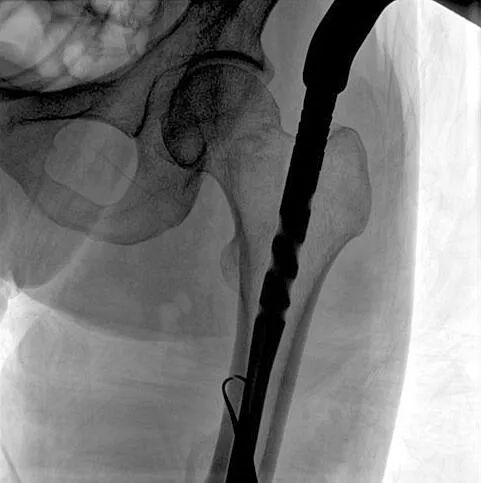

患者:男性,43歲,左股骨干骨折髓內釘內固定術

術中使用普愛醫療大平板一體式C形臂進行透視,判斷骨折情況及克氏針、髓內釘等金屬植入物的位置,進行調整。C形臂準確的術中定位,大大縮短了手術的時間,減輕了患者的痛苦,輔助手術順利完成。

在進行髓內釘內固定術時,醫生需要同時觀察到入釘點和骨折部位的情況,普愛醫療大平板一體式C形臂采用30CM×30CM的平板探測器,能夠呈現更廣闊的成像面積,滿足大部分長骨髓內釘內固定術的攝片需求。

術中定位準確、出血量少,術后影像顯示股骨移位糾正,恢復良好力線,手術效果良好。